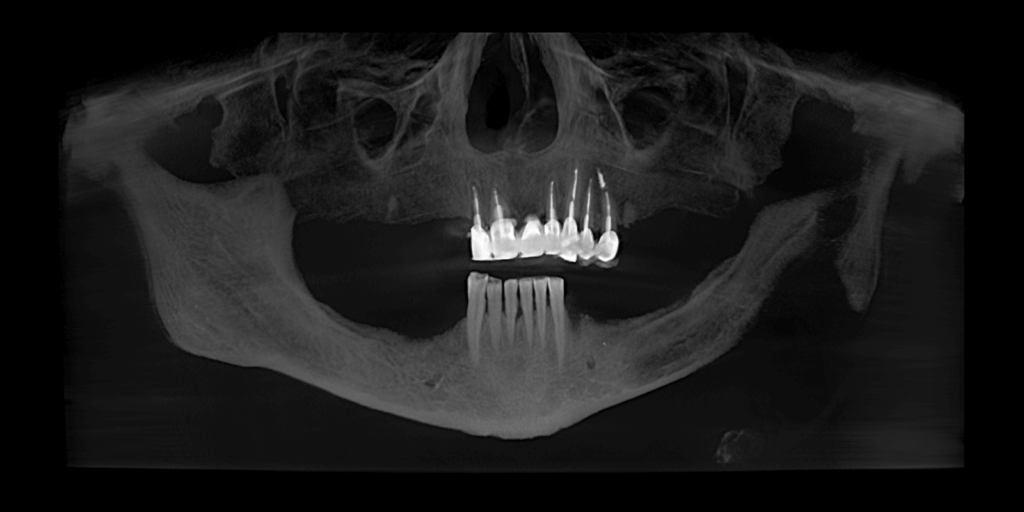

В нашу клинику обратилась пациентка с жалобами на эстетический дефект зубов, и невозможность пережевывать пищу. Врач провел предварительный осмотр и назначил КТ. На полученном КТ-снимке наблюдался металлокерамический мостовидный протез на верхней челюсти, керамическое покрытие на мостовидном протезе было повреждено (со сколами) в результате естественного износа из-за длительной эксплуатации.

- Установить 9 зубных имплантов: 5 – на верхней челюсти и 4 – на нижней.

- Остаток корня зуба 3.4 удалить одноэтапно с имплантацией.

- Имплантацию зубов выполнить двухэтапной техникой.